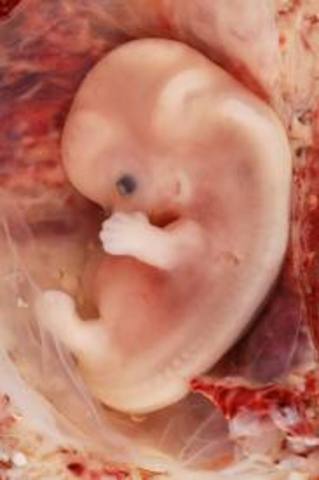

• week 5

week 5

The amniotic fluid is being built up.

The embryo grows from a tiny speck about 2mm - the size of a pin head.

By the end of the week the embryo will have more than doubled in size to about 4-5mm.

The egg has now completely grown into the mucous membrane of the uterus which covers the egg, the umbilical sac and the amniotic fluid cavity.

A fibrin clot closes the hole to the uterus cavity.

The placenta is developing.

The embryo starts receiving oxygen and nutrition through the placenta.